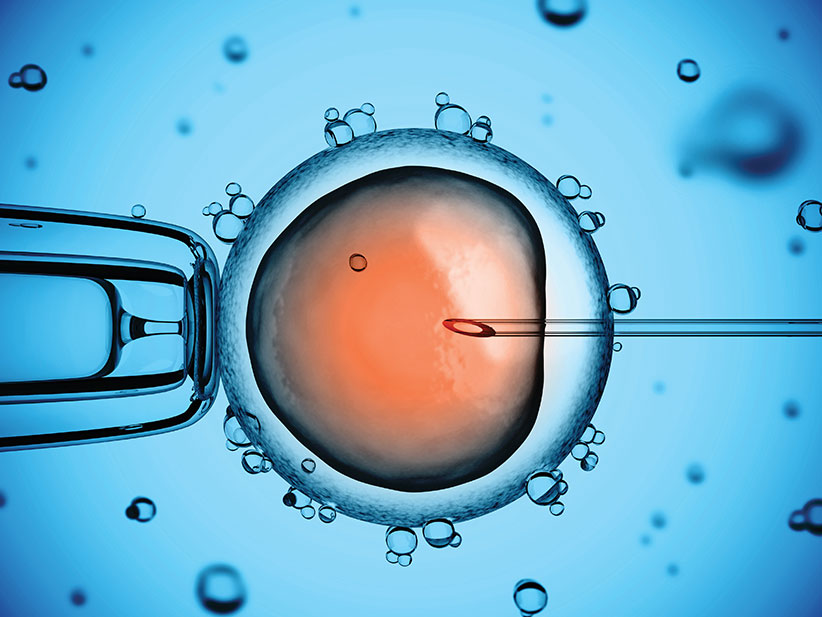

Ин витро оплождане

Ин витро е процес, при който се изваждат яйцеклетки от яйчниците на жената, оплождат се от сперматозоиди на мъжа в лабораторни условия, оплодените яйцеклетки се отглеждат няколко дни до развитието на ембриони, които се пренасят в матката на жената.